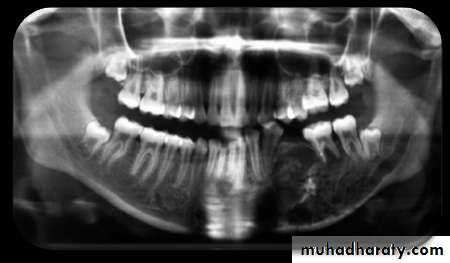

• Mandible is more prone than maxilla as vascular supply is readily compromised.• Cropped panoramic radiograph of suppurative osteomyelitis at the right side of mandible.

• After sufficient bone resorption irregular, mot- eaten areas of radiolucency may appear.

• RADIOGRAPHIC FEATURES

• May be normal in early stages of disease . Do not appear until after at least 10 days.• Radiograph may demonstrate ill-defined radiolucency.